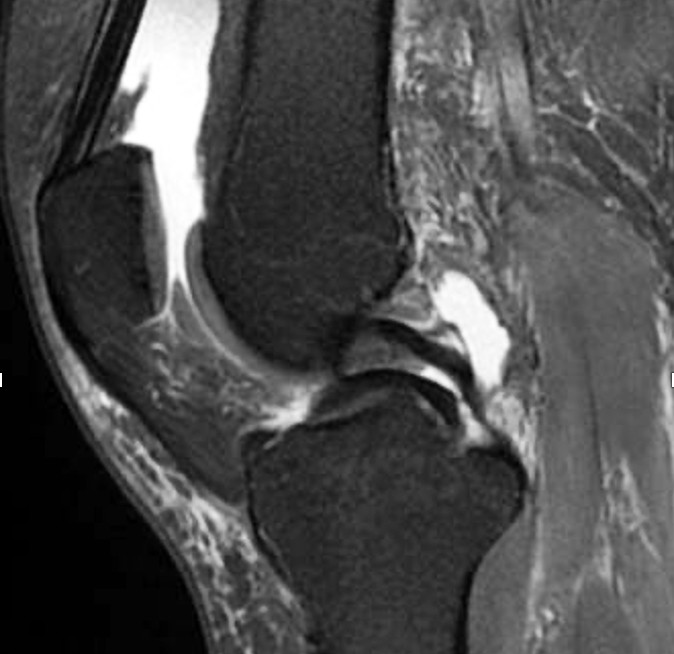

Traumatiske meniskskader ses oftest hos yngre aktive personer og er ofte høyenergiskader, ikke sjelden assosiert med skade av fremre korsbånd (23). Typiske traumatiske rupturer kan være «bøttehankformede» (longitudinelle, vertikale (figur 2, figur 3) og kan ligge innslått mot eminensene), radiale, eller flappformede. Innslåtte bøttehankrupturer kan gi både ekstensjons- og fleksjonsinnskrenkning, og tidlig reponering og sutur er indisert for å hindre skrumpning og destruksjon av meniskvevet.

Meniskrotrupturer er skader i eller nær bakre innfesting av meniskene mot tibia (bakre rotrupturer) (figur 2) (24). Mediale rotrupturer ses oftest i degenerative knær som ledd i en artroseutvikling, og laterale rotrupturer ses oftest hos yngre pasienter med skade av fremre korsbånd. Rotrupturene medfører ofte mer smerter og hydrops enn andre meniskskader.

Sekundære funn på MR kan være meniskekstrusjon eller ledsagende benmargsødem (25). Ekstrusjon skyldes at menisken enten er rumpert radiært eller rotnært (traumatisk) eller tøyd (degenerativt) og dermed skvist ut av leddspalten. Konsekvensen er at menisken helt eller delvis mister sin funksjon – på lik linje med en fullstendig kirurgisk fjerning av hele menisken (26). Meniskekstrusjon er antatt å gi økt risiko for raskt progredierende artrose (27).

Traumatiske menisk- og rotrupturer opereres artroskopisk med reponering av menisken og fiksasjon med diverse typer suturer o.l. (figur 4). Degenerative rotrupturer opereres hvis det ikke foreligger uttalte artroseforandringer på leddbrusken. Postoperative rehabiliteringsprotokoller divergerer avhengig av type ruptur og reparasjon, men en tommelfingerregel er vektavlastning med krykker i seks uker og fysioterapiveiledet styrketrening. Huksitting er tillatt etter tre måneder, og man kan returnere til idrett og aktiviteter etter 5–7 måneder (29). I litteraturen er det beskrevet varierende grad av tilheling, men en metaanalyse av bøttehankrupturer viste 77 % tilheling (30). Ved rotrupturer er det vist opptil 93 % tilheling etter to år (31).